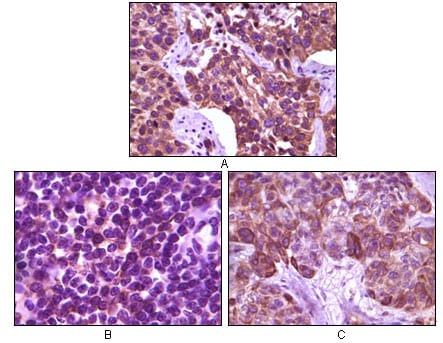

分类: 科研抗体货号: 20104别名: BP-1; 4EBP1; 4E-BP1; PHAS-I; MGC4316; EIF4EBP1应用: IHC反应种属: Human